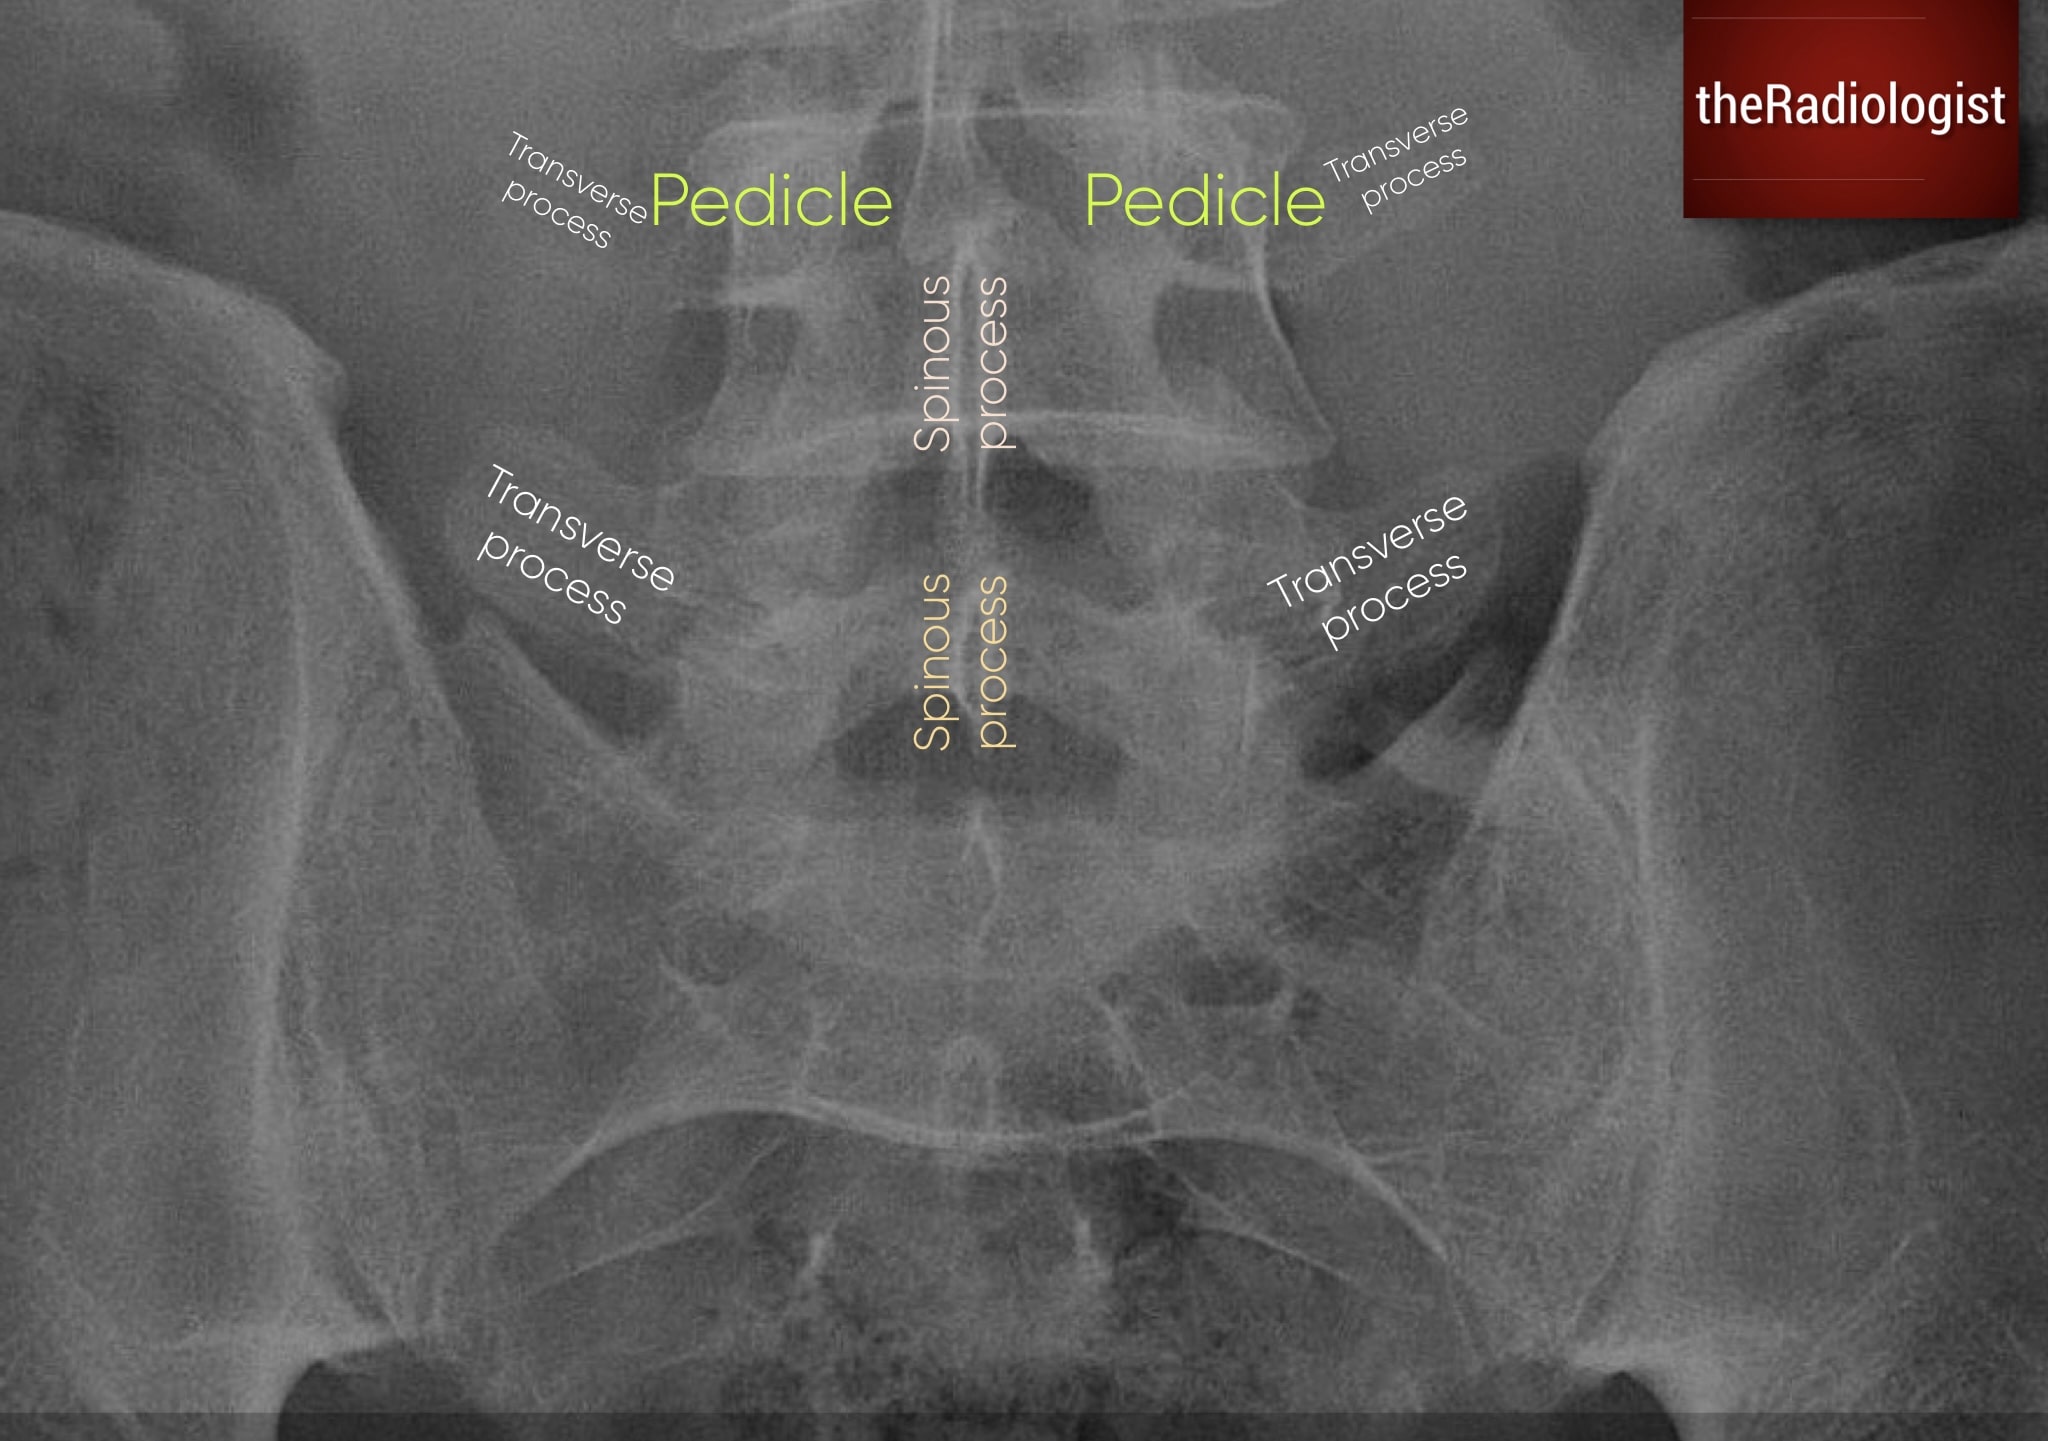

P: Pedicles and lumbar spine

The upper part of the AP pelvic film often captures the lower lumbar vertebrae. Always review these for cortical disruption, lytic lesions, or incidental fractures. Don’t miss pathology here just because the film was done for the pelvis. Remember a missing pedicle (’winking owl sign’) could represent an aggressive lesion.

Don’t forget to check the vertebrae and posterior elements within the lower lumbar spine.

KEY POINT

Don’t miss a lumbar spine fracture or lesion on a pelvic X-Ray!

A missing pedicle can mean an aggressive lesion (‘winking owl sign’).